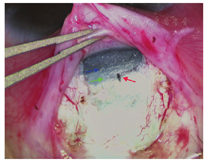

手术的关键点是如何找到Schlemm管做小梁切开。为了准确找到Schlemm管,巩膜瓣的制作部位十分重要[6]。由于患眼角膜缘扩张明显,制作巩膜瓣应在扩张的角膜缘之后进行,否则会错过偏后的Schlemm管(图1);此外,巩膜瓣的厚度也是寻找Schlemm管的关键。Schlemm管的外部标志是灰蓝色小梁网带与白色巩膜的连接处。需制作较厚的板层巩膜瓣(一般为2/3巩膜厚度或以上),才能在巩膜床上清晰辨认3个重要的解剖部位,即透明角膜区域、白色巩膜区域及灰蓝色小梁网带(图2)。

在灰蓝色小梁网带与白色巩膜结合处,即为Schlemm管走向。在此位置前0.5 mm至后0.5 mm之间,做长度为0.5~1.0 mm的垂直切口,细心寻找切口深处黑点,若黑点处有房水溢出或少量出血,提示Schlemm管外壁已被切开。建议在高放大倍数显微镜下,缓慢、仔细沿着切口壁加深切口,定位Schlemm管。